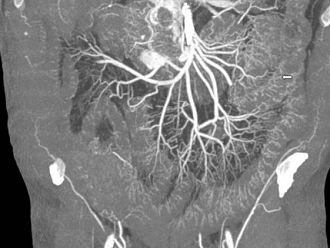

Гадолиниевите контрастни вещества се използват за усилване на контраста с цел подобряване на качеството на изображение при магнитно-резонансно изследване. Такива изследвания на тялото се базират на магнитното поле, образувано от водните молекули в тялото. След инжектиране гадолиният взаимодейства с водните молекули. В резултат на това взаимодействие, водните молекули произвеждат по-силен сигнал и така се постига по-голяма яркост на изображението.